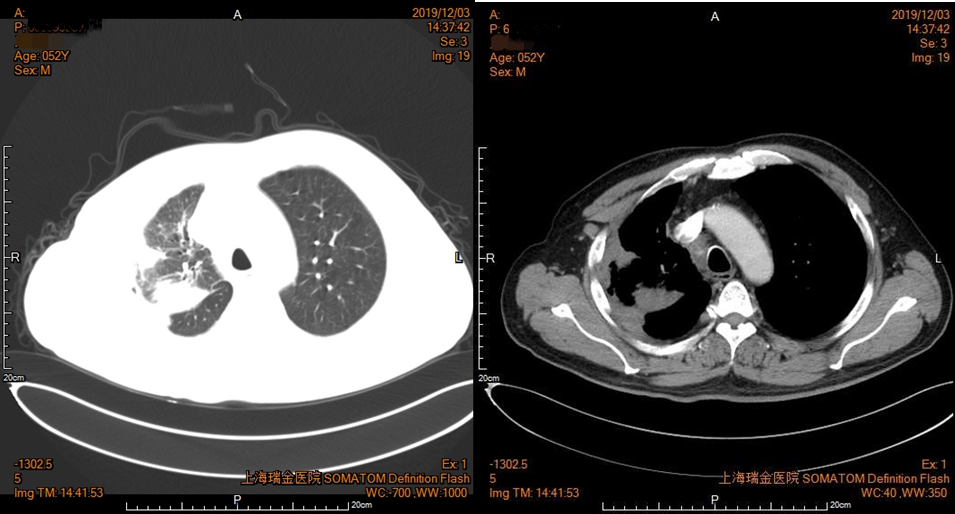

2019年10月10日胸部增强CT(图5):右肺门及上叶Ca伴右肺上叶阻塞性肺不张治疗后较前片(7月26日)范围减小,纵隔淋巴结肿大,左肺上叶肺气肿伴肺大疱。

图5 患者胸部CT影像资料(2019年10月10日)

2019年12月3日胸部增强CT(图6):右肺门及上叶Ca伴右肺上叶阻塞性肺不张治疗后较前片(10月10日)范围减小,纵隔淋巴结肿大,左肺上叶肺气肿伴肺大疱。

图6 患者胸部CT影像资料(2019年12月3日)